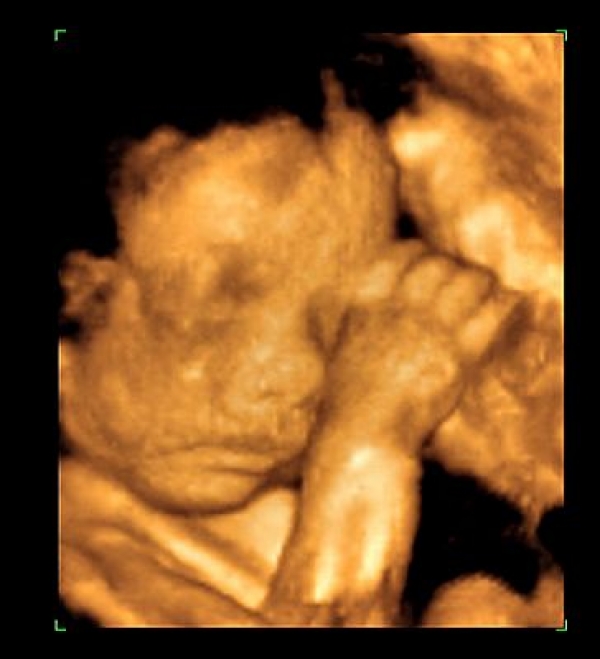

Galéria k článku Potraty v Nitre opäť povolené!